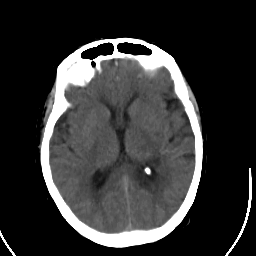

Stroke CT #2 -- Slice #13

[Home][Help][Clinical] Slice 13